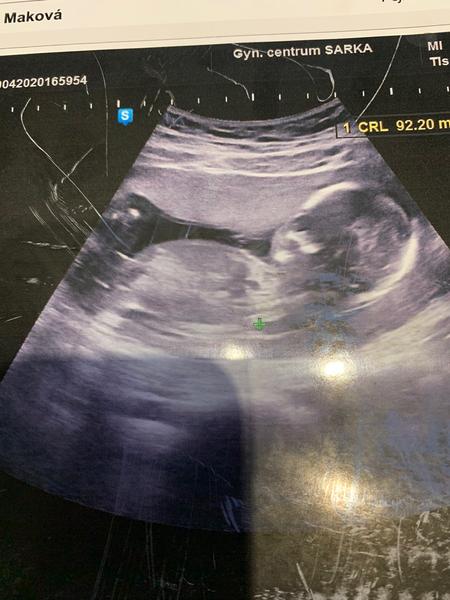

Ahoj maminky,určitě jste tady dost zkušené..pozorovala jsem už podobné diskuze,tak se taky obracím 😁 vidíte tam chlapečka nebo holčičku? Predevcirem na ultrazvuku mi doktorka říkala, ze na 70% kluk ale ze ji muže zmást pupeční šňůra,ze si mám spíše počkat do 20 týdne,ale ze je to spíše chlapeček. Na obrazovce jsem ale neviděla okolo nožicek žádný pytlík nebo něco co by bylo podobné varlatám,spis jen takový malinký šourek.. Co myslíte vy?? Tady to sice nejde moc poznat ale snad se něco překvapivého dozvim😁 Samozřejmě je mi to jedno,hlavně ze je zdravoucke❤️

Bohuzel to z toho nejde moc poznat 🙂 ale kdyz to srovnam s nasim ultrazvukem taky bych rekla chlapecek 🙂 nam ho bohuzel potvrdily az v 21tt na 2 screeningu... Drive taky ani tuk :D a souhlasim ze 3D je spolehlivy tam nam ho potvrdily opet podruhe a potreti jeste jednou ve 38tt v porodnici na kontrole 🙂)) takze bych jeste pockala do toho 2 screeningu a i dr mi rikal ze ten je nejpresnejsi a je to tam videt nejlepe ❤

I kdyby se tady na to nasel nejaky odbornik, tak na tehle fotce to neni absolutne kde videt.

@marinagilanyi počkala bych na 3D,jestli ho budou dělat,to je jistější. Ale tenhle snímek nezabírá moc dobře tu "ostře " sledovanou oblast 😁takže já tam nic nevidím. Náš malý měl pytlíka znát už od 12tt,jsem se schválně koukla a na další genetice to už jen potvrdili ,to jsem byla už po tom 20tt,jestli si dobře pamatuji